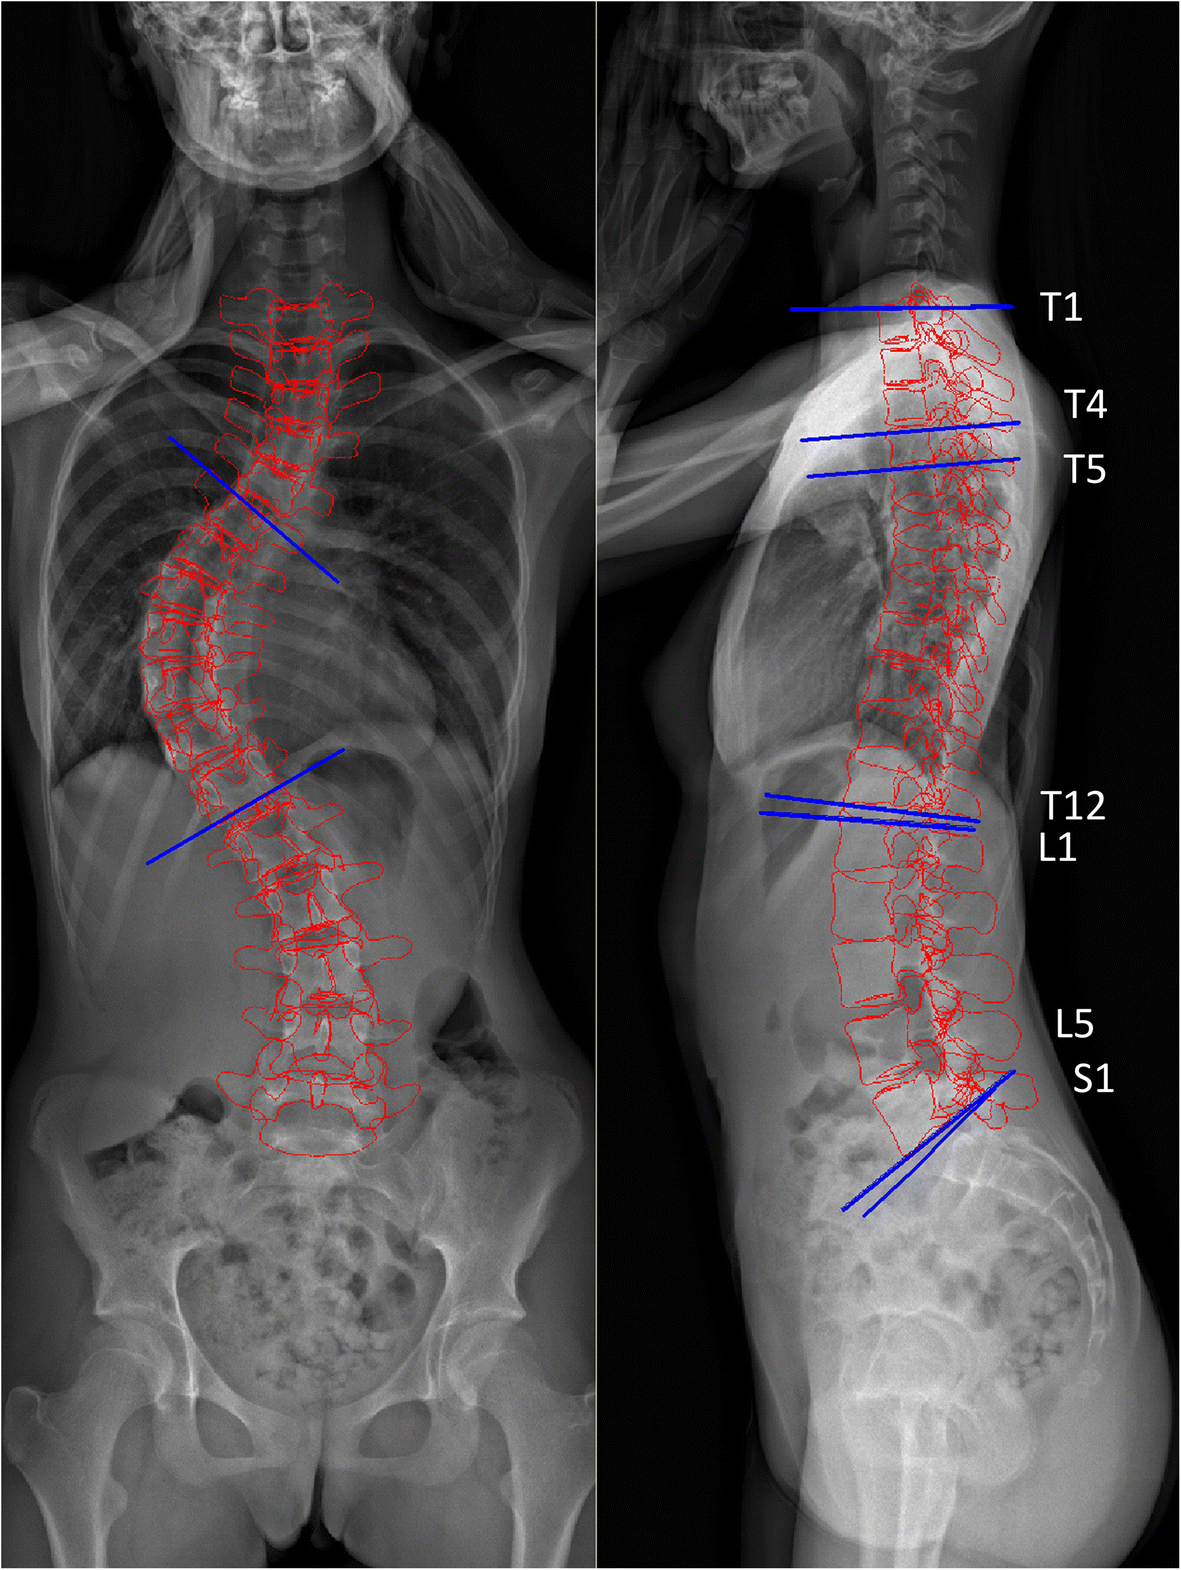

في دراسة شملت 126 طفلًا ومراهقًا مصابين بانحناء صدري أيمن، قام الباحثون بتحليل:

شكل العمود الفقري من الجانب

نتائج محاكاة رقمية باستخدام نماذج العناصر المحدودة (Finite Element Models)

النتائج كانت واضحة:

كل نوع من أنواع التقوس الجانبي للظهر أنتج نوعًا محددًا من اعوجاج العمود الفقري.

وكانت العلاقة بين أشكال التقوس السهمي وأنواع الاعوجاج قوية جدًا (p<0.001).

الأشعة الجانبية (Lateral X-ray)

الأشعة الجانبية خصوصًا مهمة لأنها تكشف تفاصيل دقيقة عن شكل العمود الفقري من الجانب.